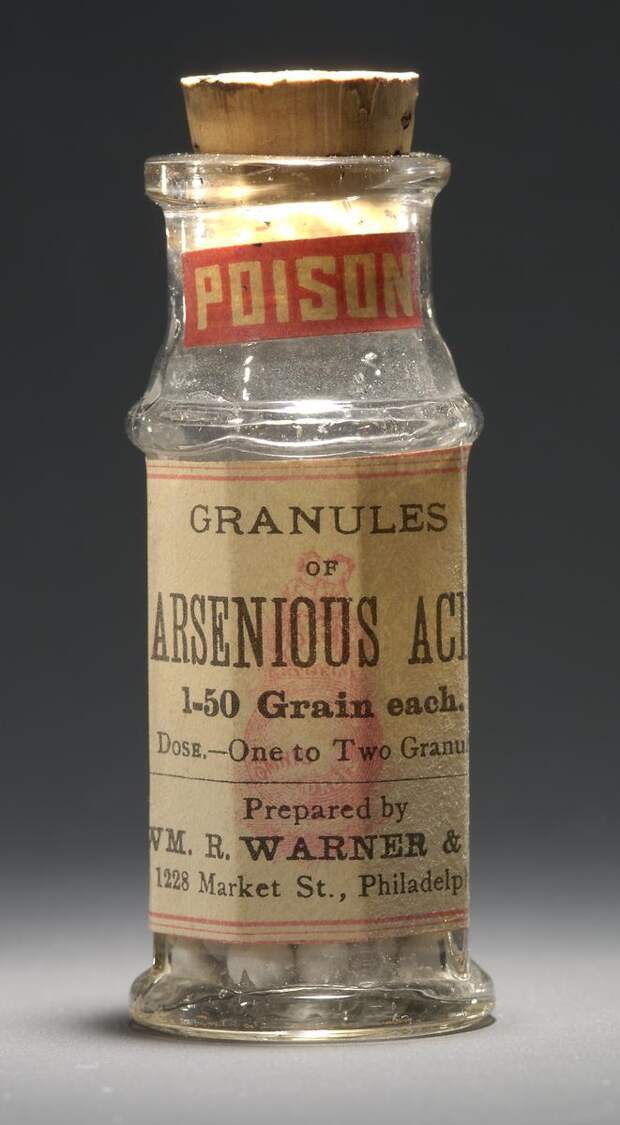

В 19 веке было модно есть мышьяк, чтобы «придать лицу цветущий вид, глазам – блеск, а телу – привлекательную округлость». Приём мышьяка, конечно же, регламентировался целым набором правил – луна должна быть прибывающей, первый приём – только одно зёрнышко (пока не выработается сопротивляемость), и если уж вы начали, то должны продолжать есть эту гадость всю жизнь – иначе смерть.

Правда, были и побочные эффекты – мышьяк накапливается в щитовидной железе и вызывает зоб. А иногда и смерть. Но когда речь идёт о красоте, кого это может остановить…